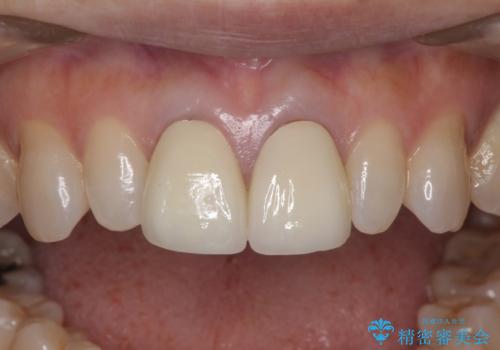

セラミック治療と根管治療を行いました。

金属を使用したメタルボンドクラウンが入っていたため、いつかオールセラミックにしたいときに根管治療も行ったほうが良いとご提案し、今回行いました。

就寝時マウスピース(約5000円別途)の使用をおすすめしました。

色について

歯と歯肉の境目の色は、歯自体が黒くなっている場合、完全にカバーすることは難しいです。